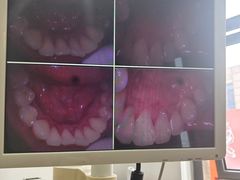

• 圣贝口腔(海淀店)

• -圣贝口腔(海淀店)